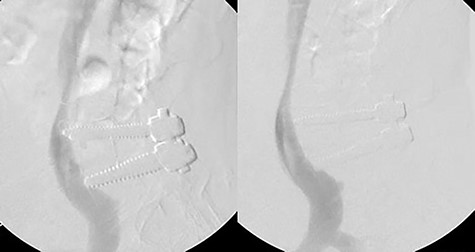

During the procedure, the patient was placed supine and a venous sheath was placed in the right femoral vein by vascular surgery. After turning the patient to prone position, the sheath was secured away from the hip bolster with tape to assure the line remained unkinked and functional (Fig. 2). A prone venogram was taken, which showed the right sided hardware indenting the IVC and right common iliac vein. A small posterior lumbar incision was made 3.5 cm to the right of midline over the hardware, which was exposed via a Wiltse approach. The right sided screws and rod were removed (Fig. 3). After removal, bleeding through the pedicle screw tracts was not observed. With the patient still in the prone position, a venogram was taken immediately after screw removal and showed no extravasation of contrast. It also showed that there was no longer indentation on the IVC and the right common iliac vein (Fig. 4). Thus, no further intervention was required. The incision was closed and the venous sheath removed. The postoperative course was uncomplicated.

Venogram showing right hardware indenting right common iliac vein and IVC (left). Postoperative venogram displays indentation no longer present after hardware removal (right).